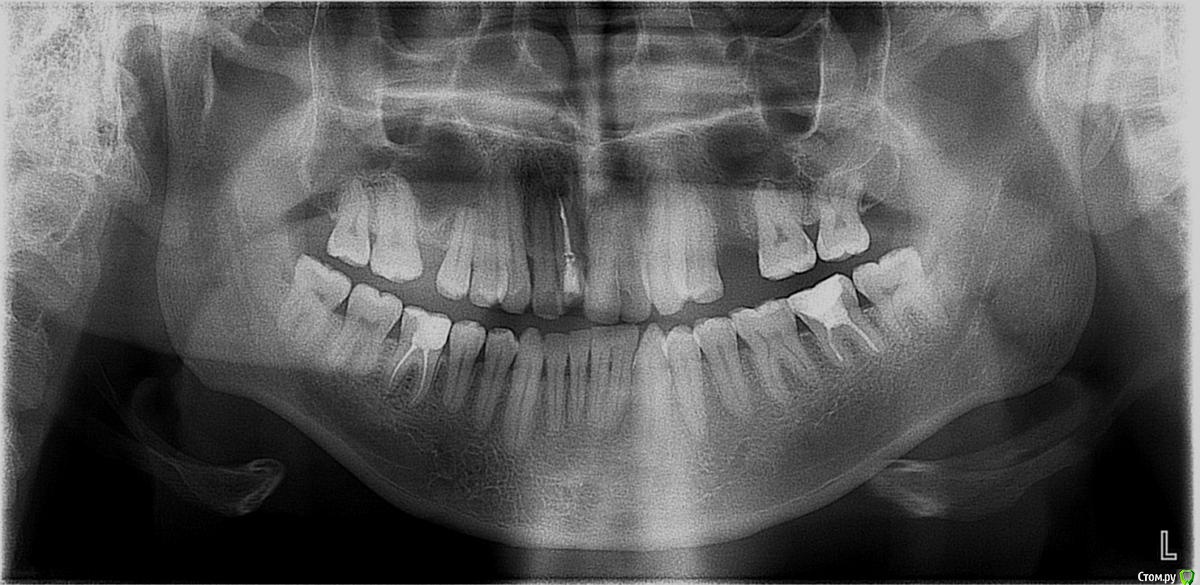

Nick-ev Опубликовано 31 марта, 2018 Автор Поделиться Опубликовано 31 марта, 2018 нужно смотреть фото/снимки Единственное что нашел май 2016 года, как раз удален левый зуб мудрости и зубы начали уходить в его сторону. а это что было до брекетов октябрь 2013 года... Ссылка на комментарий